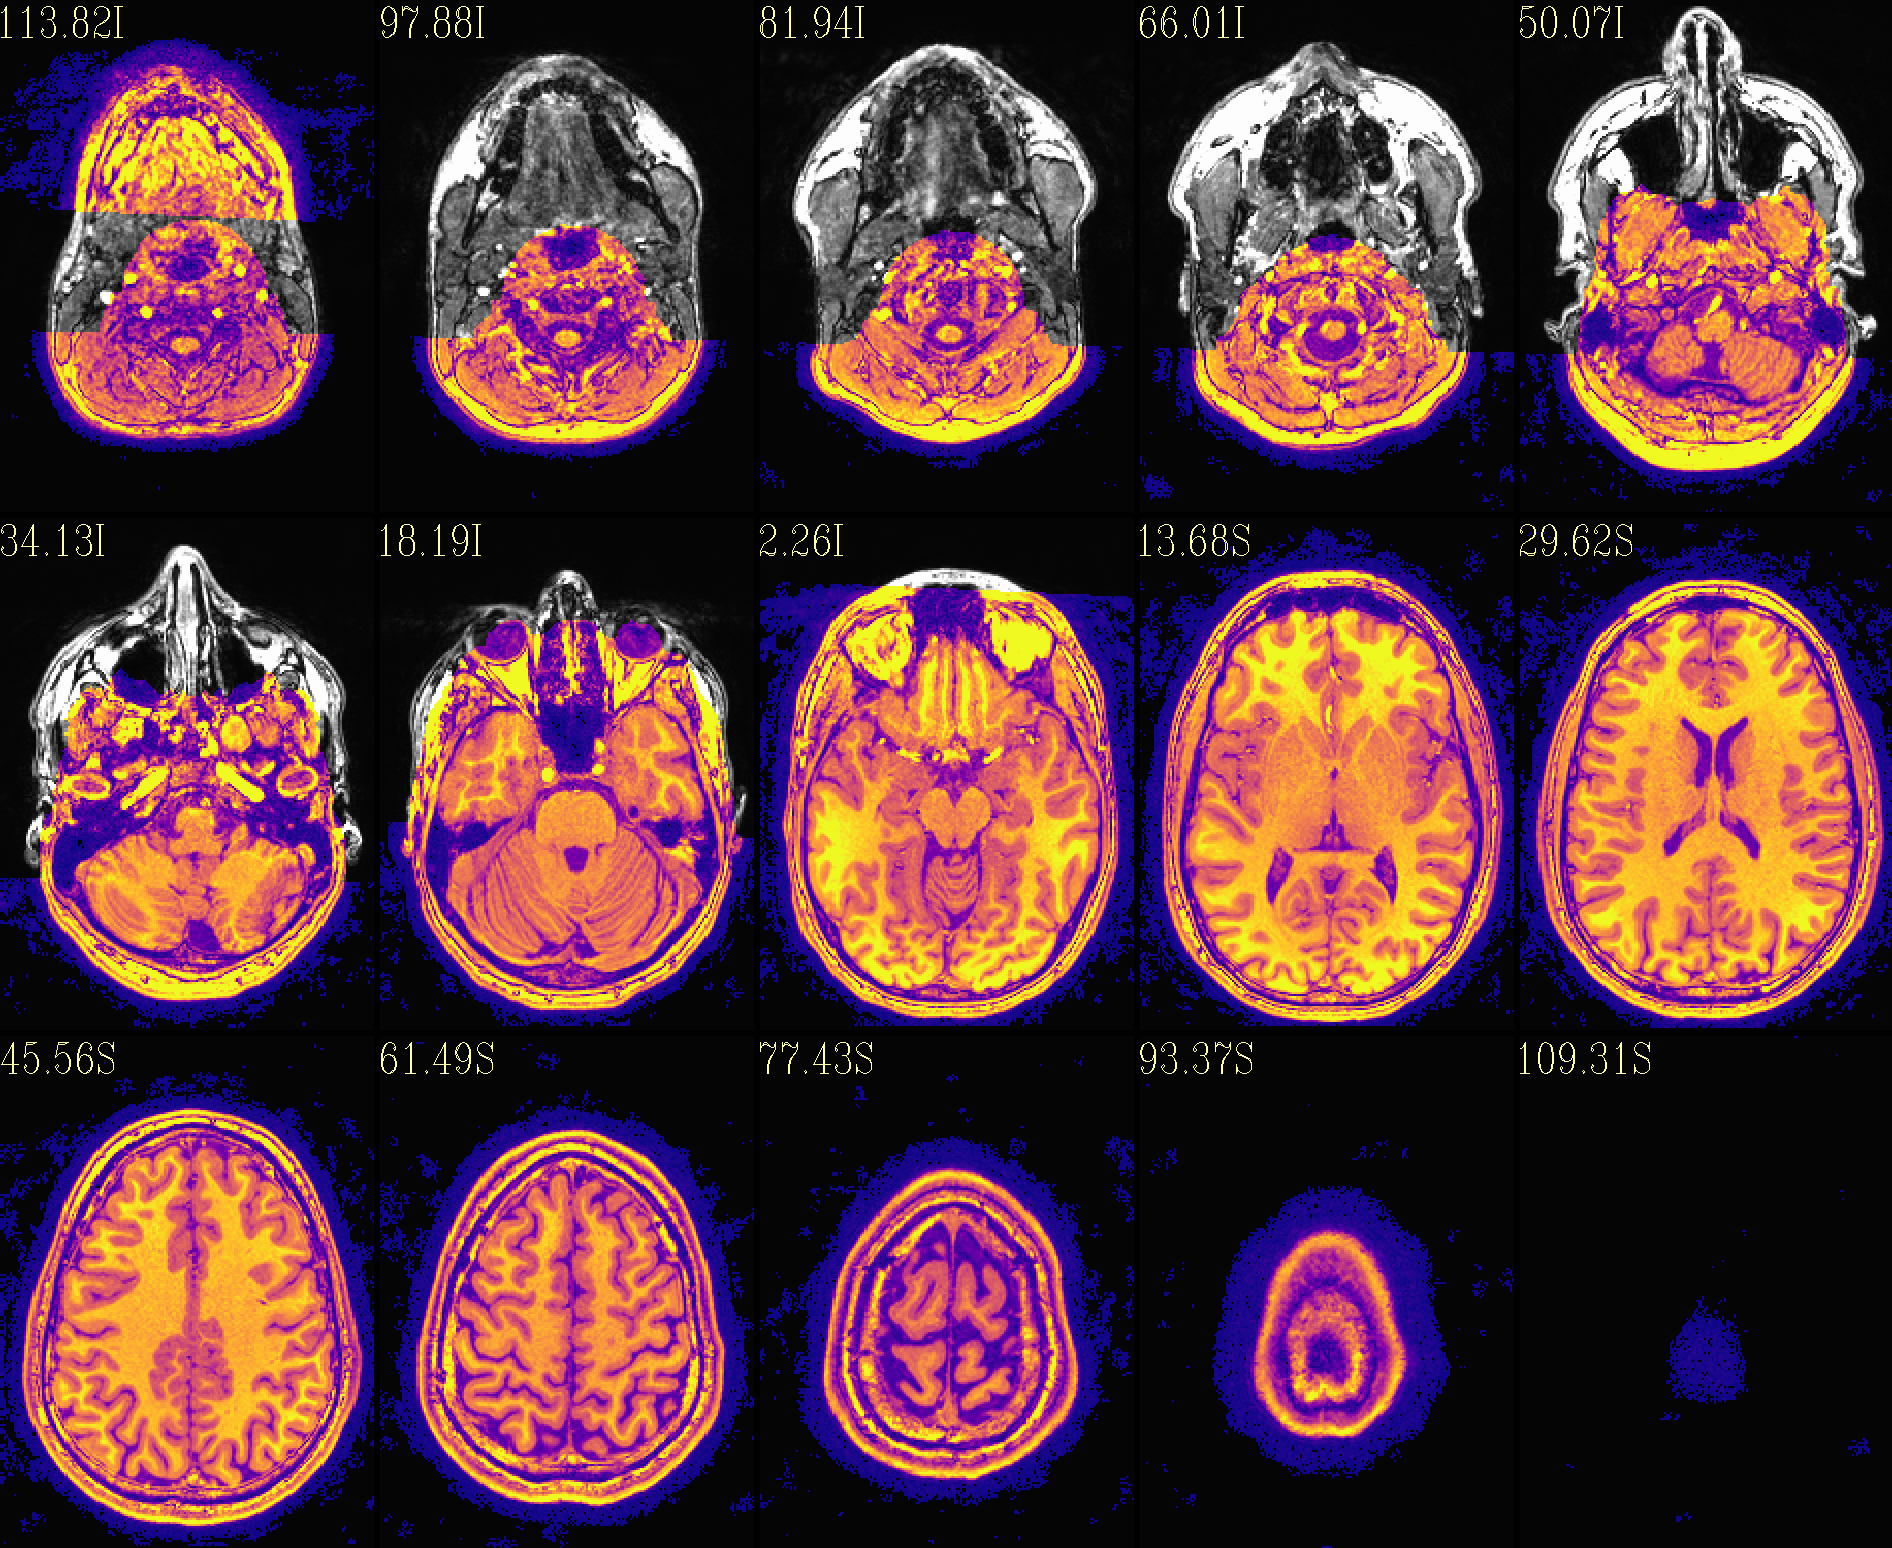

QC image files are produced in sets of 3: one each of axial, coronal and sagittal slices. They display the face and/or face_plus regions used, as well as the new dataset overlayed on the original, for comparison.

The output images of the above command are presented here. Based on

the prefix given, they would each be created in a subdirectory called

anat_QC.

The ‘face’ region for replacement or zeroing (overlayed on orig input) |

The ‘deface’ volume, overlayed on orig input |

|

The ‘reface’ volume, overlayed on orig input |

The ‘reface_plus’ volume, overlayed on orig input |